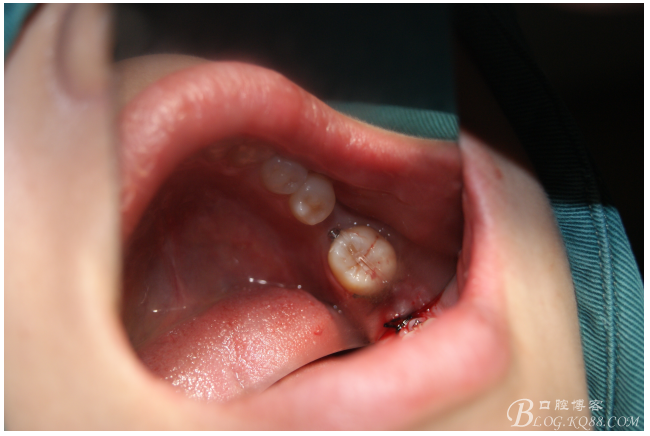

處理:必蘭麻局部麻醉切開37遠中牙齦,植入mini支抗釘一枚,37近中鄰面粘舌側(cè)扣,皮鏈輕力牽引,3周更換。

三月后37扶正

植入5.0X10mm植體